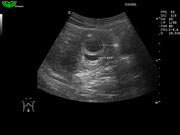

D3C60L 3.5МГц, конвексный.

2.0МГц - 5.8 МГц. Применения: абдомиальное обследование, акушерство, гинекология, обследование районной блокады нерва, осуществление и управление биопсией. |

Отображение гармоники ткани (THI)

Не только улучшает пространственное разрешение, но и значительно повышает контраст изображения. Специально для полных пациентов, чтобы врач более точно ставил диагноз.

- Улучшает пространственное и контрастное разрешение изображения.

- Доступно для всех датчиков.

- Возможность выбора до 5 полос частот.